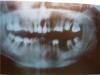

Nicki Опубликовано 3 декабря, 2009 Поделиться Опубликовано 3 декабря, 2009 Около 3-х месяцев назад мне удалили 6-ой правый нижний зуб. Вначале думали сделать мост, но затем врач предложил имплантант. Пришлось подождать некоторое время, пока выросла бы костная ткань и выяснилось бы, можно ли ставить имплантант.За это время мне запломбировали 7 и 8 зуб рядом. Побывав у имплантолога, он сказал, что в принципе можно ставить имплантант, но он посоветовал бы все же мост.У меня к сожалению наблюдается немножечко шатание зубов, как мне сказали, то есть есть подвижность кости и десны, надеюсь я правильно выразилась.В общем, все 3 врача - лечащий врач, ортопед и имплантолог - почти все колеблются в решении, какой метод выбрать для меня, а я тем более не знаю, что мне выбрать.Если делать мост, то надо будет на 5-6-7-8, без 8-го говорят не обойтись.Если бы можно было бы, то я вовсе ничего не делала бы, тем более не заметно со стороны, что у меня нет там зуба. К сожалению, говорят, что и 7-ой зуб не ахти в хорошем положении.А один из врачей (со стороны) даже сказал, что мост ставить нельзя, а с имплантацией надо повременить, так как надо выяснить в итоге что останется.Почему так сложно сделать выбор? Лично для меня - имплантация звучит как сложная операция, а мост, это еще надо будет тронуть и 5-ый зуб, ... а вдруг у меня заболеет 7-й зуб, что мне тогда делать. Не потеряю ли я разом несколько зубов из-за моста? Ссылка на комментарий

mafuSail Опубликовано 4 декабря, 2009 Поделиться Опубликовано 4 декабря, 2009 с седьмым зубом плохо то, что костной ткани вокруг него практически не осталось, с этим и связана его подвижность.4 и 5 - под коронки по-любому, так как нервы из них удалены, а это означает тонкие стенки и возможность сколов. коронки предотвратят их.возможно стоит предварительно перед этим попытаться перелечить коневой канал в пятерке - не запломбирован до конца. одномоментная имплантация или нет - решать хирургу.я б сначала удалил семерку, подсыпал бы костного материала в область 6 и 7 - чтоб восстановить объем, подождал бы 4-6 месяцев, и потом уже ставил бы 2 импланта. восьмерка действительно может послужить как опорой под временную конструкцию на это время. седьмой сверху депульпируется и покрывается коронкой - так как он выдвинут вниз и будет в дальнейшем мешать протезированию внизу.6 вверху под коронку. Ссылка на комментарий